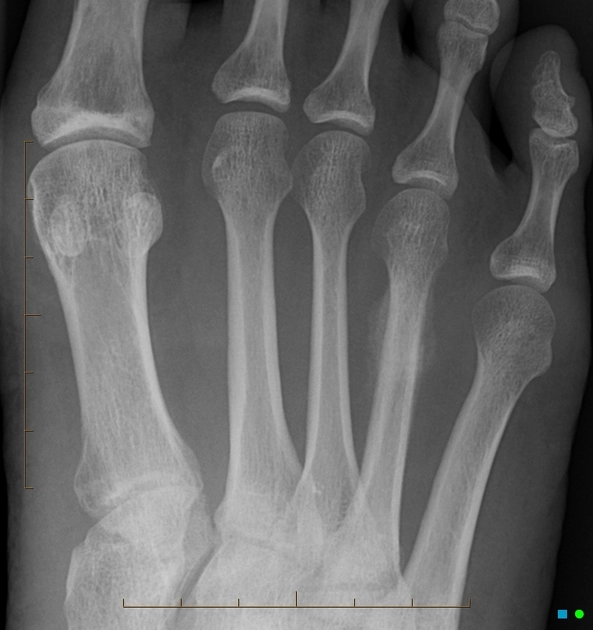

Gãy Jones (Gãy đầu gần xương bàn chân số 5)

16/03/2026

Gãy bong lồi củ xương bàn chân số 5 (pseudo-Jones fracture)

Gãy do mỏi ở xương bàn chân số 5 (Stress fracture of the 5th metatarsal)